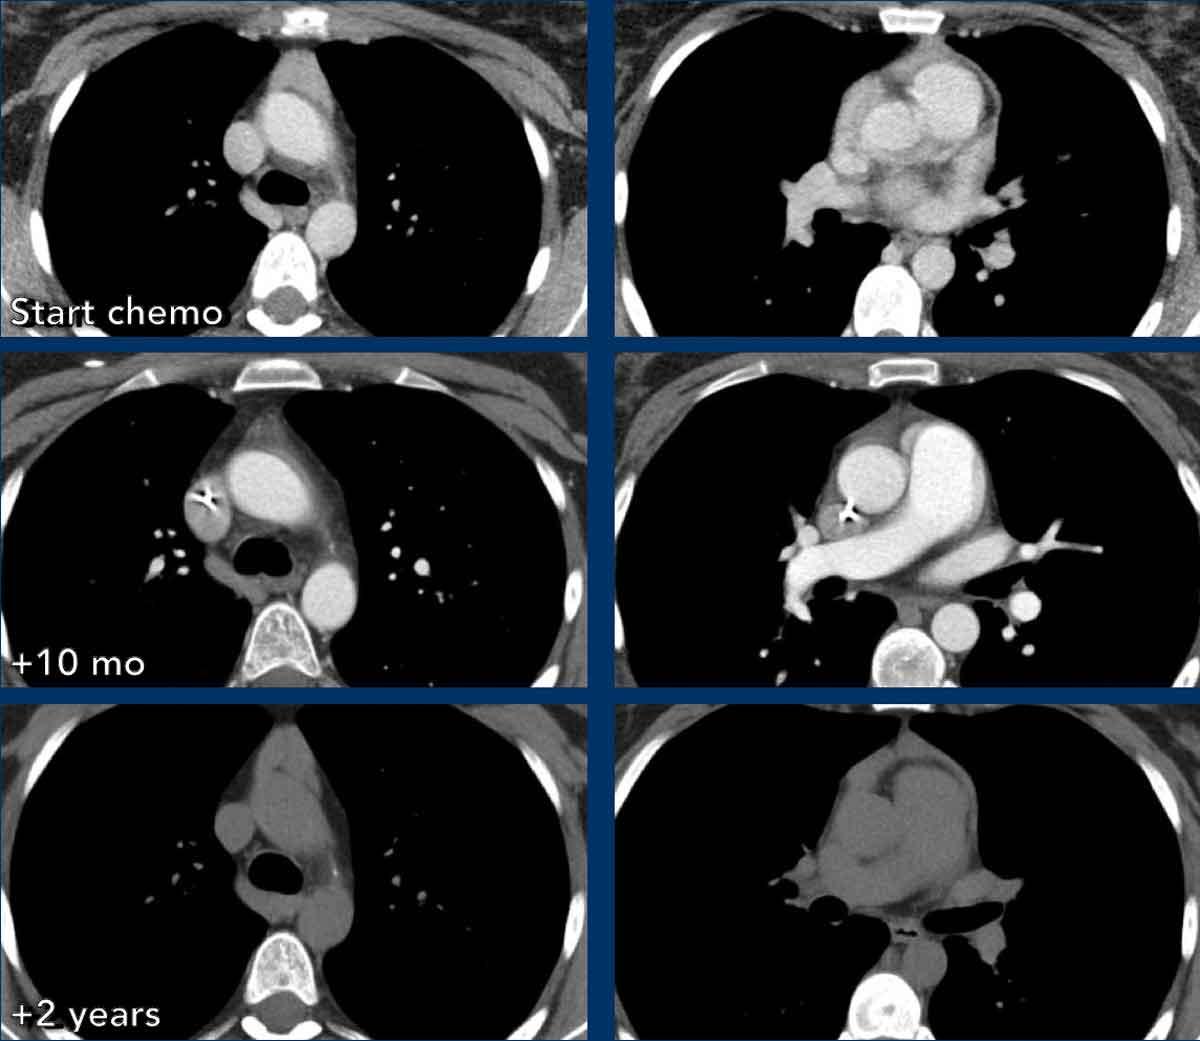

Ca lâm sàng 2

Các hình ảnh này của một bệnh nhân nam 43 tuổi có đau ngực.

Hình ảnh

Có một khối ở trung thất trước mạch máu.

Bờ không đều và tổn thương dương tính trên PET-CT.

Thảo luận

Chẩn đoán có khả năng nhất là thymoma, có thể là thể xâm lấn hoặc thậm chí là ung thư tuyến ức.

Tiếp tục xem phim chụp tiền phẫu hai tháng sau…

Hai tháng sau, một phim chụp tiền phẫu được thực hiện.

Rõ ràng là tổn thương đã nhỏ hơn.

Tuy nhiên, phẫu thuật viên vẫn quyết định cắt bỏ tổn thương và kết quả giải phẫu bệnh là ung thư tuyến ức.

Chúng tôi không có giải thích rõ ràng cho những gì đã xảy ra ở đây.

Có một số phản ứng trong mô mềm xung quanh khối u trên phim chụp đầu tiên (mũi tên).

Có thể đã có tình trạng viêm trong khối u và các mô xung quanh, khiến khối u trông lớn hơn.